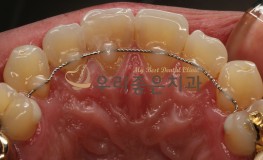

치료전후사진

충치치료

2019-03-16